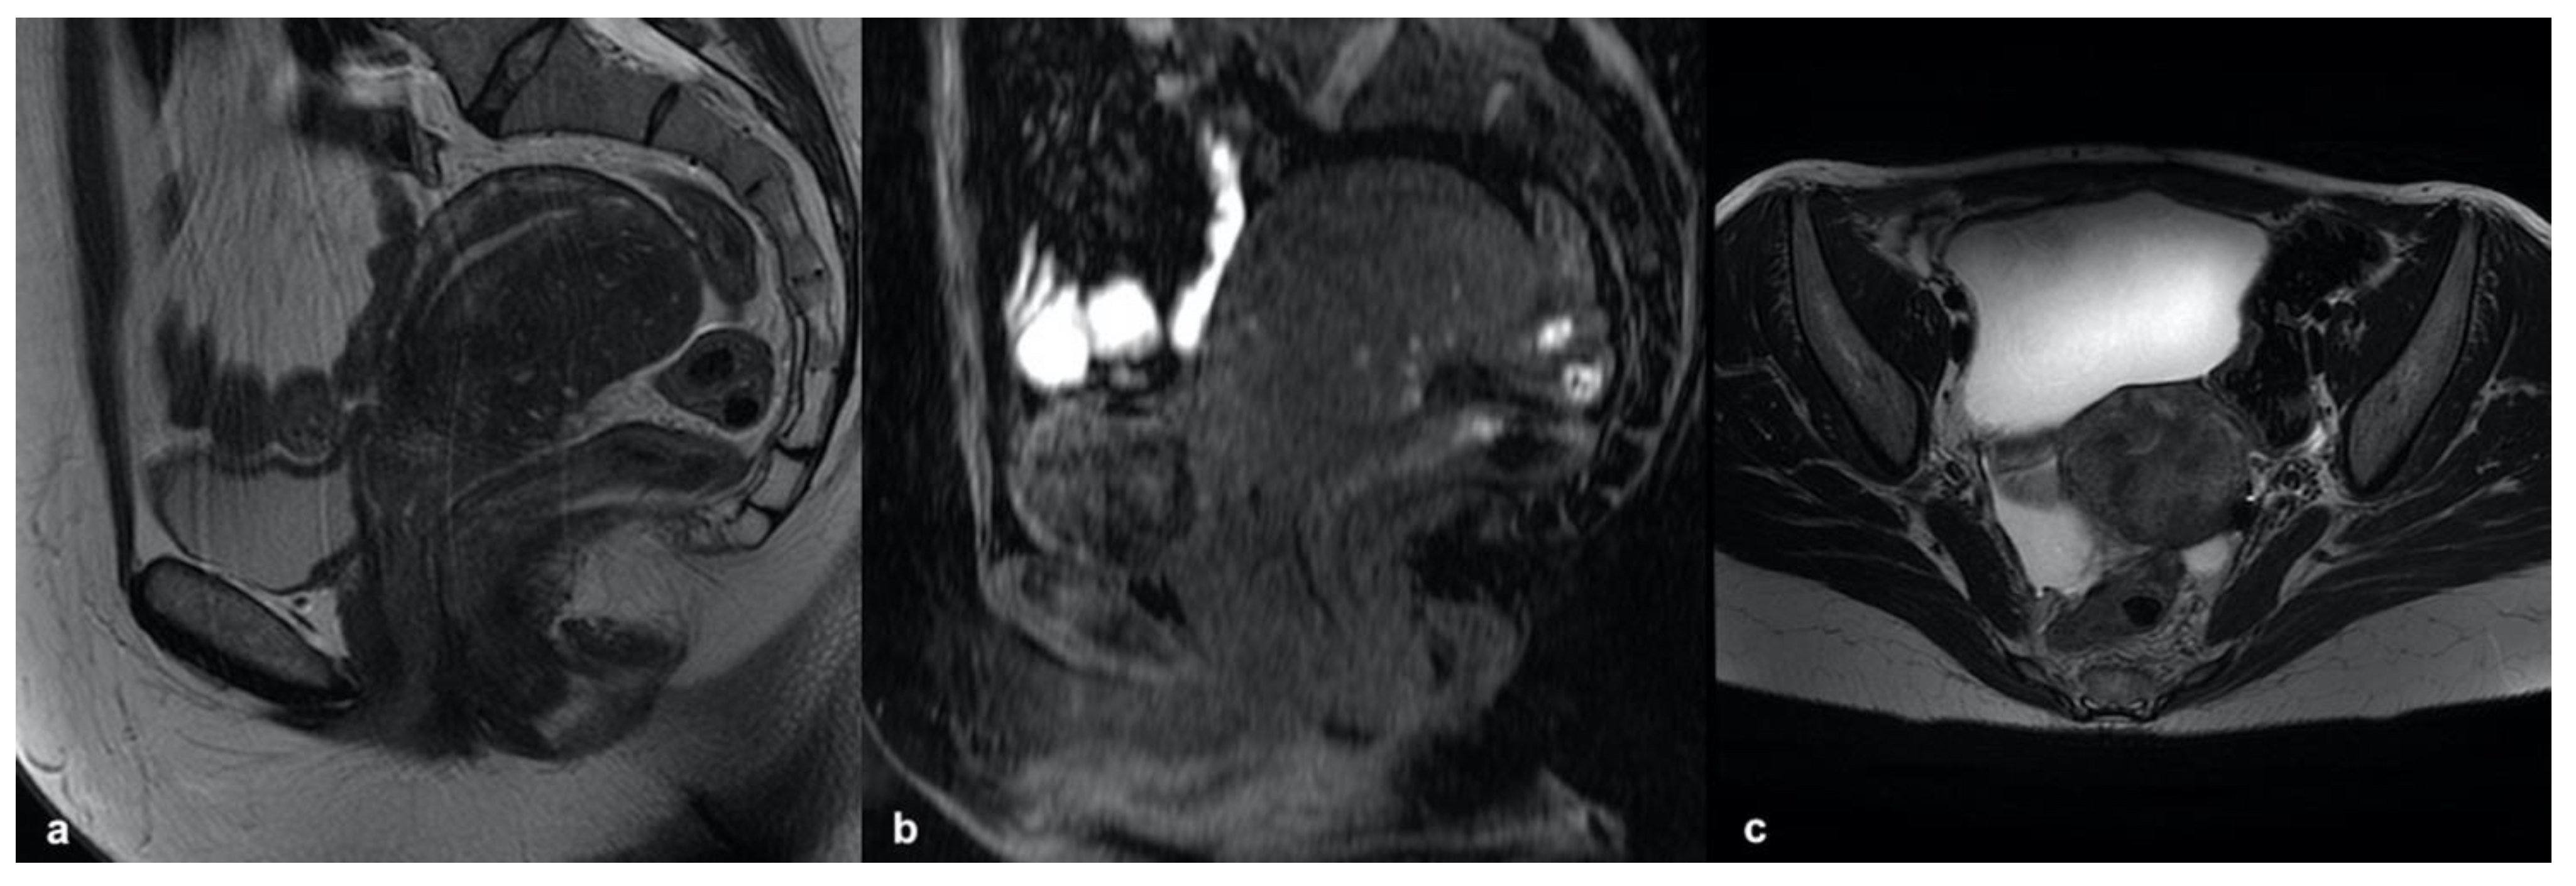

3.5.2. Accessory Cavitated Uterine Mass (ACUM)

3.5.3. MELF Endometrial Carcinoma